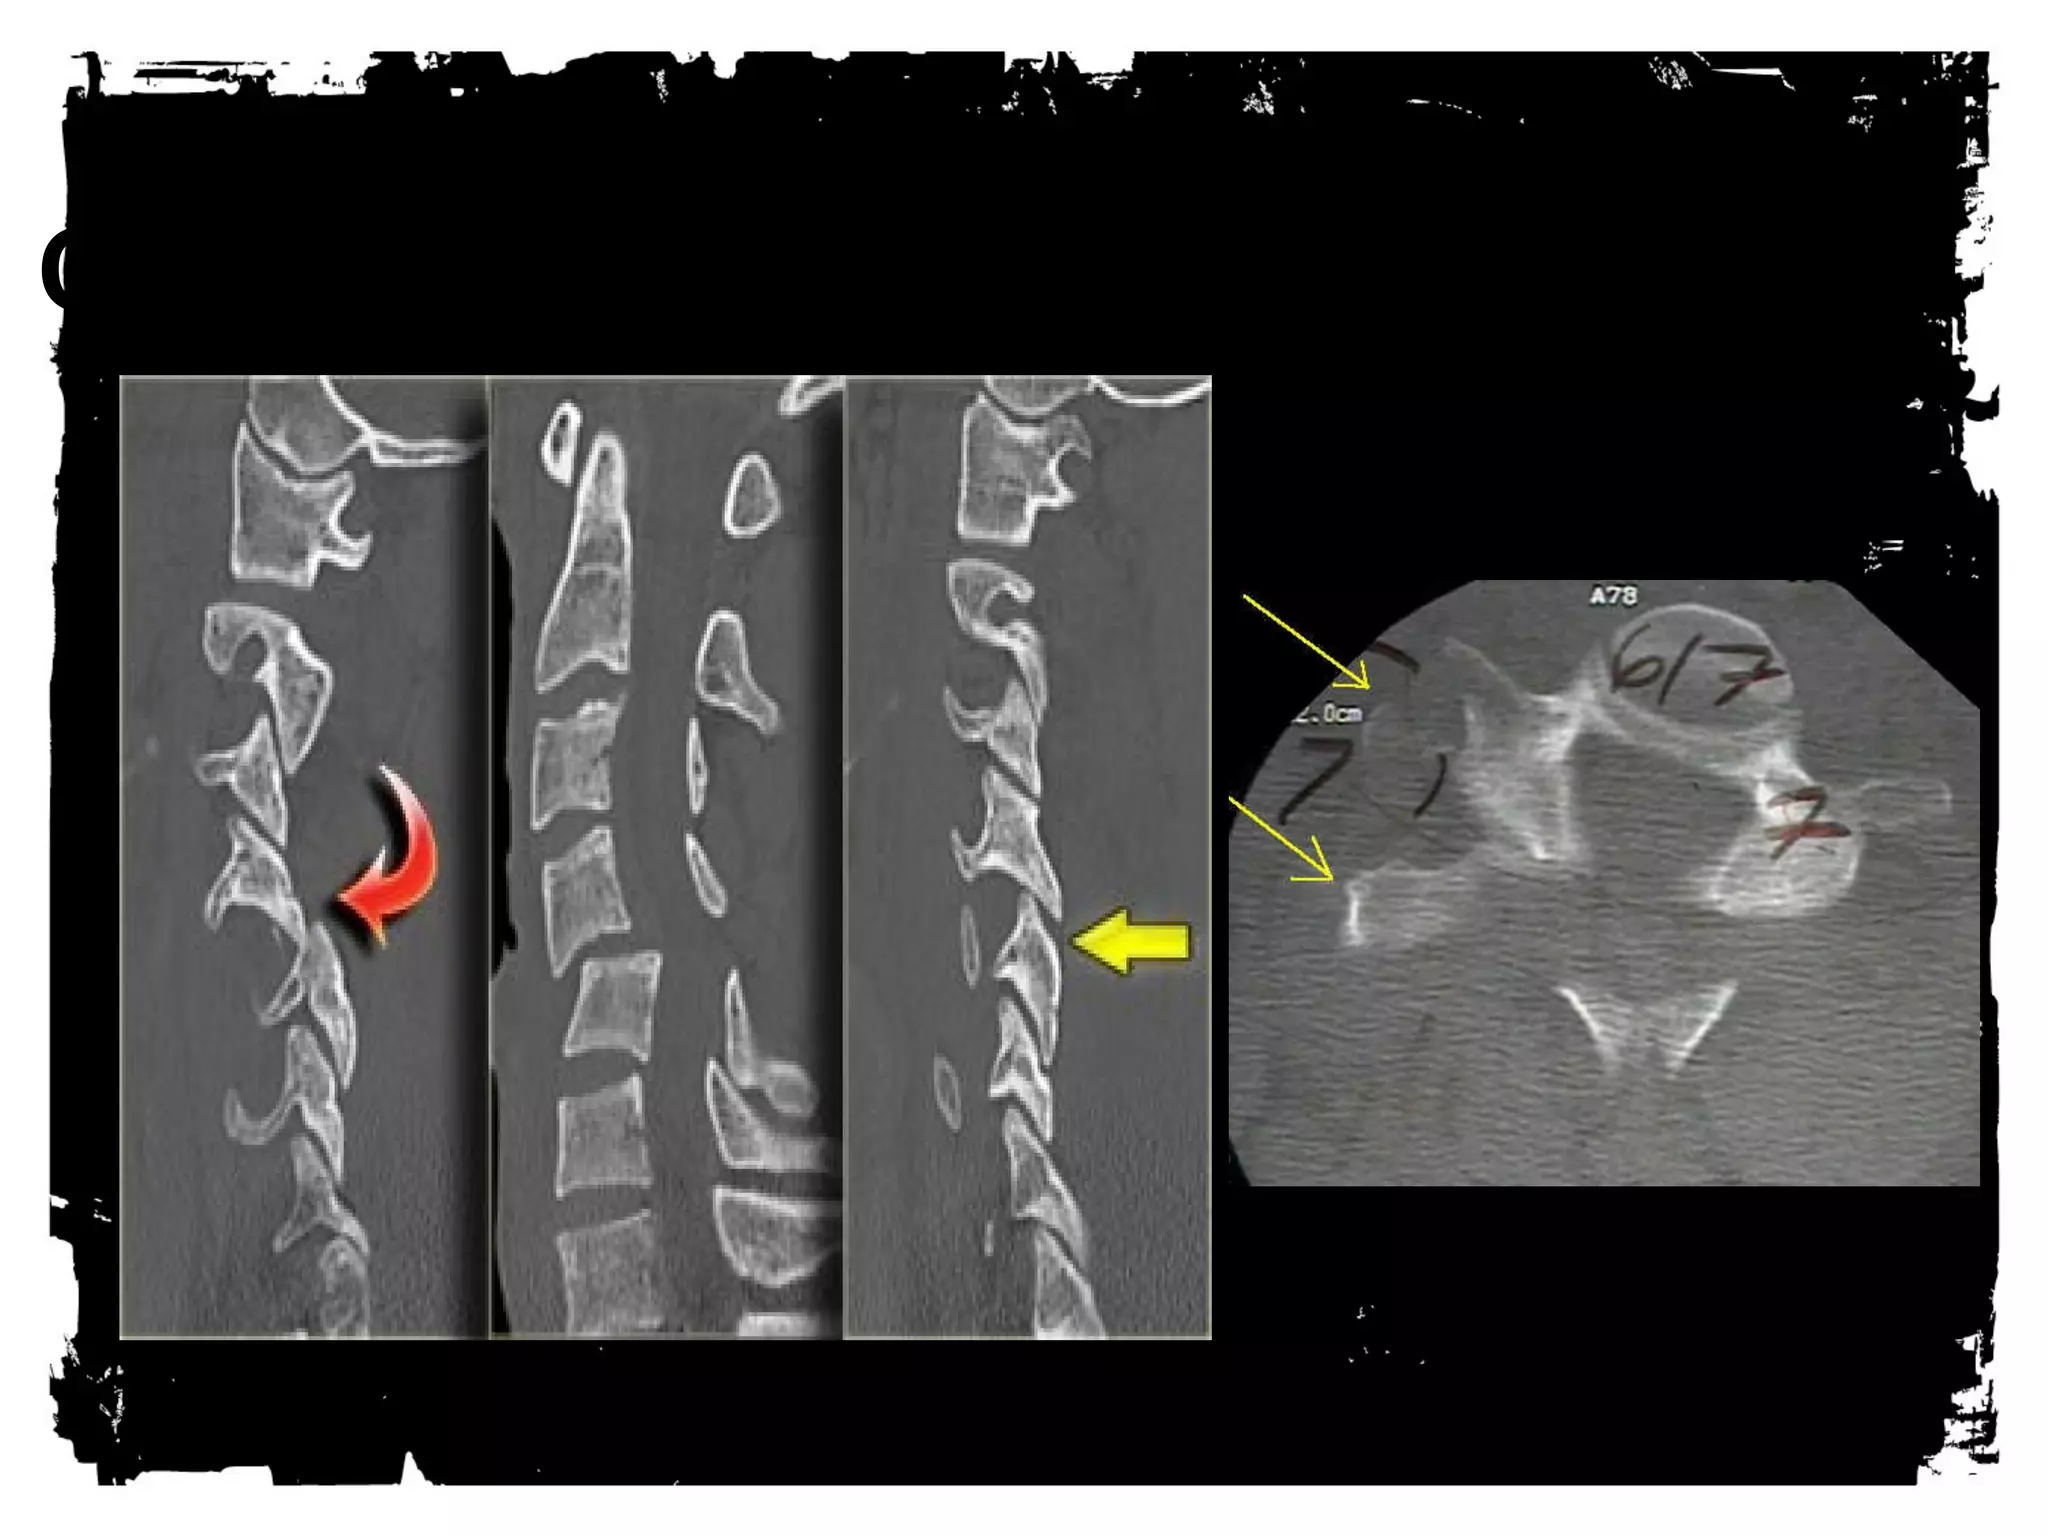

Thoracic Spine Injuries

Rigid

Spinal canal narrower than cervical or lumbar spine

Large spinal cord diameter relative to canal

diameter increases the risk of cord injury

Injury, usually significant (complete), less common

than in other regions

Association between fractures of the thoracic spine

and severe pulmonary injuries, mediastinal

hemorrhage